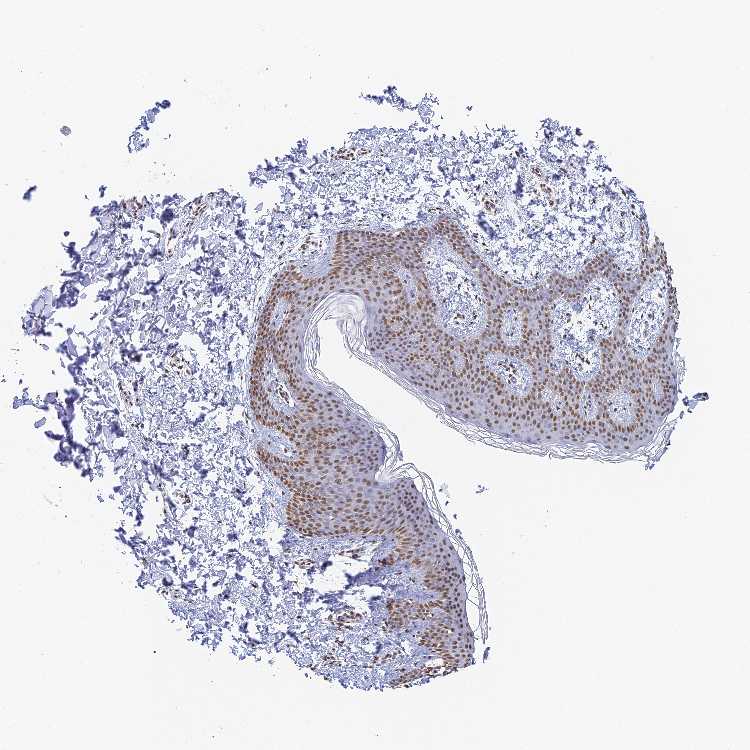

SKIN 1 - Antibody stainingi

Antibody staining in the annotated cell types in the current human tissue is reported as not detected, low, medium, or high, based on conventional immunohistochemistry profiling in selected tissues. This score is based on the combination of the staining intensity and fraction of stained cells.

Each image is clickable and will lead to virtual microscopy that enables deeper exploration of all samples and also displays staining intensity scores, fraction scores and subcellular localization as well as patient and tissue information for each sample.

Antibody HPA045657

Langerhans Medium

Fibroblasts Medium

Keratinocytes Medium

Melanocytes Medium